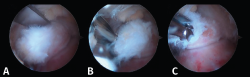

Figura 4. A: imagen artroscópica que muestra el ligamento peroneo-astragalino posterior (LPAP) (1); B: resección del LPAP con un sinoviotomo orientado medialmente contra la cara lateral del proceso posterolateral del astrágalo (PPA) (2); C: cara lateral del PPA después de la resección del LPAP.

- Primer paso: retirar el LPAP, completamente en caso de PPAH y parcialmente en caso de OT. La resección del tejido ligamentoso se realiza apoyando la ventana del sinoviotomo contra el lateral del PPA (Figuras 4 A, B y C).

- Segundo paso: eliminar el tejido blando en la parte superior del PPA. La ventana del sinoviotomo se gira 90° para apoyarse sobre la parte superior del PPA. Con ello, se realiza la artrotomía tibioastragalina y se escinde la cápsula hipertrófica de la articulación posterior. Es importante realizar movimientos en plano horizontal para preservar la continuidad del ligamento intermaleolar y evitar una artrotomía de trazo vertical que podría seccionar inadvertidamente dicho ligamento (Figuras 5 A, B y C).

- Tercer paso. El sinoviotomo se gira ahora para que la ventana vuelva a mirar la cara medial del PPA. En este momento, el tendón FHL permanece medial al sinoviotomo y opuesto a su ventana. Podemos así seccionar el retináculo del FHL con el sinoviotomo o mediante una pinza de tipo basket (Figuras 6 A, B y C).

Figura 6. A y B: liberación del retináculo del flexor hallucis longus (FHL) (1); C: evaluación del interior de la vaina del FHL (2).